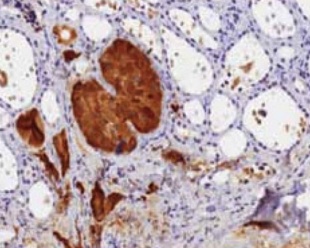

Figure 6 . Epithelial cells with an organoid and trabecular pattern with positive immunohystochemical staining for chromogranin .